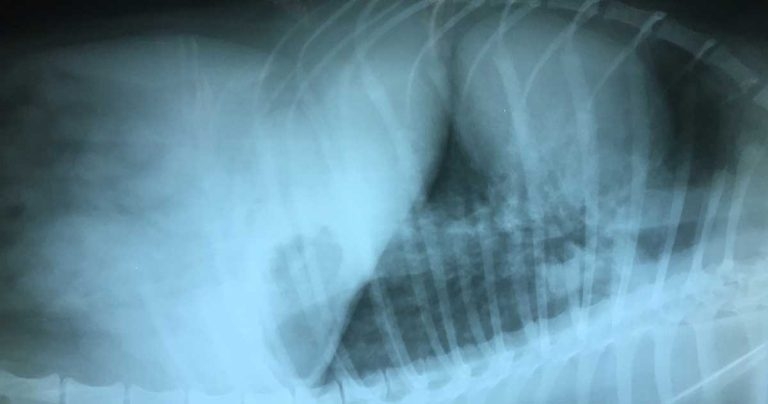

Figure 1. A right lateral thoracic radiograph taken at presentation showing a mixed lung pattern, with some impression of nodular change.

Thoracic radiographs showed a patchy bronchoalveolar lung pattern – a lateral radiograph is shown in Figure 1.